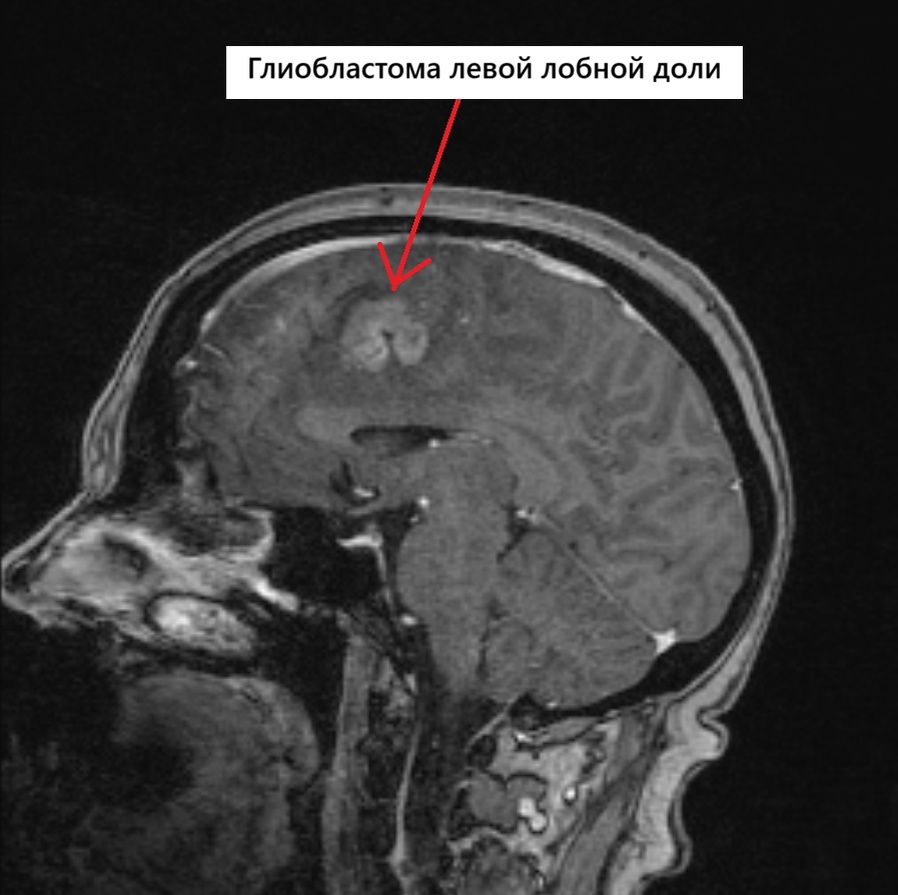

МРВ Π³ΠΎΠ»ΠΎΠ²Π½ΠΎΠ³ΠΎ ΠΌΠΎΠ·Π³Π° ΠΏΠ°Ρ†ΠΈΠ΅Π½Ρ‚ΠΊΠΈ с глиобластомой Π»Π΅Π²ΠΎΠΉ Π»ΠΎΠ±Π½ΠΎΠΉ Π΄ΠΎΠ»ΠΈ (Π²ΠΈΠ΄ сбоку)

ΠŸΡ€ΠΈ МРВ Π³ΠΎΠ»ΠΎΠ²Π½ΠΎΠ³ΠΎ ΠΌΠΎΠ·Π³Π° Π±Ρ‹Π»ΠΎ выявлСно ΠΎΠ±ΡŠΡ‘ΠΌΠ½ΠΎΠ΅ ΠΎΠ±Ρ€Π°Π·ΠΎΠ²Π°Π½ΠΈΠ΅ Π² Π»Π΅Π²ΠΎΠΉ Π»ΠΎΠ±Π½ΠΎΠΉ Π΄ΠΎΠ»Π΅ с Π²Ρ‹Ρ€Π°ΠΆΠ΅Π½Π½Ρ‹ΠΌ ΠΎΡ‚Ρ‘ΠΊΠΎΠΌ ΠΎΠΊΡ€ΡƒΠΆΠ°ΡŽΡ‰ΠΈΡ… Ρ‚ΠΊΠ°Π½Π΅ΠΉ (Π² Π»Π΅Π²ΠΎΠΉ Π»ΠΎΠ±Π½ΠΎΠΉ Π΄ΠΎΠ»Π΅ ΠΏΠ°Ρ€Π°ΡΠ°Π³ΠΈΡ‚Ρ‚Π°Π»ΡŒΠ½ΠΎ опрСдСляСтся патологичСскоС ΠΎΠ±Ρ€Π°Π·ΠΎΠ²Π°Π½ΠΈΠ΅ Π½Π΅ΠΏΡ€Π°Π²ΠΈΠ»ΡŒΠ½ΠΎΠΉ Ρ„ΠΎΡ€ΠΌΡ‹, с нСсколько Π½Π΅Ρ‡Π΅Ρ‚ΠΊΠΈΠΌΠΈ Π½Π΅Ρ€ΠΎΠ²Π½Ρ‹ΠΌΠΈ бугристыми ΠΊΠΎΠ½Ρ‚ΡƒΡ€Π°ΠΌΠΈ, Ρ€Π°Π·ΠΌΠ΅Ρ€ΠΎΠΌ 26Ρ…18Ρ…32 ΠΌΠΌ, с Π²Ρ‹Ρ€Π°ΠΆΠ΅Π½Π½Ρ‹ΠΌ ΠΎΠ±ΡˆΠΈΡ€Π½Ρ‹ΠΌ ΠΏΠ΅Ρ€ΠΈΡ„ΠΎΠΊΠ°Π»ΡŒΠ½Ρ‹ΠΌ ΠΎΡ‚Π΅ΠΊΠΎΠΌ, Ρ€Π°ΡΠΏΡ€ΠΎΡΡ‚Ρ€Π°Π½ΡΡŽΡ‰ΠΈΠΌΡΡ Π½Π° Π»ΠΎΠ±Π½ΡƒΡŽ ΠΈ Ρ‚Π΅ΠΌΠ΅Π½Π½ΡƒΡŽ Π΄ΠΎΠ»ΠΈ, Ρ€Π°Π·ΠΌΠ΅Ρ€ ΠΎΡ‚Π΅ΠΊΠ° 116Ρ…46Ρ…55 ΠΌΠΌ. Π’ височной Π΄ΠΎΠ»Π΅ Π·ΠΎΠ½Π° ΠΎΡ‚Π΅ΠΊΠ° Π±Π΅Π»ΠΎΠ³ΠΎ вСщСства 31Ρ…23 ΠΌΠΌ.)Β